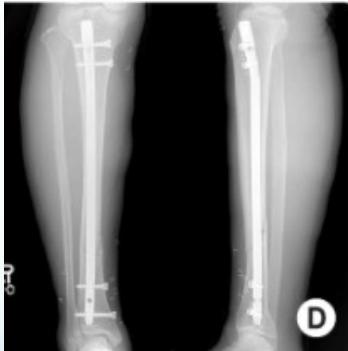

Inter-locking Nail

- Indications: Treatment of fractures of long bones

- Advantages:

- Minimally invasive

- Does not disturb fracture hematoma

- Allows early weight-bearing on lower limb